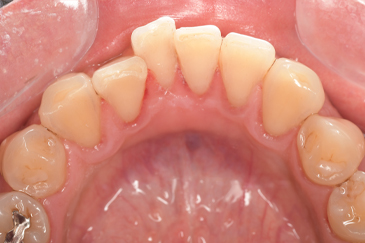

CASE 4

Before

After

基本情報

| 年齢・性別 | 52歳・女性 |

|---|---|

| 主訴 | クリーニングしたい |

| 治療内容 | スケーリング・PMTC |

| 治療期間 | 60分 |

| 治療費 | 約7,000円 |

| リスク・副作用 | 知覚過敏、歯肉退縮 |

| 治療方針 | 歯石とステインを除去して、今後は定期検診でのクリーニングと併せてガムピーリングやホワイトニングを行います。 |

| 担当者所見 | 歯肉の色素沈着が目立つため、ガムピーリングを行いながらホワイトニングを行うことをおすすめします。 |